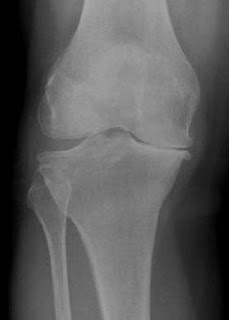

Diagnosis : Osteoarthritis of knee joint

Knee X-Ray